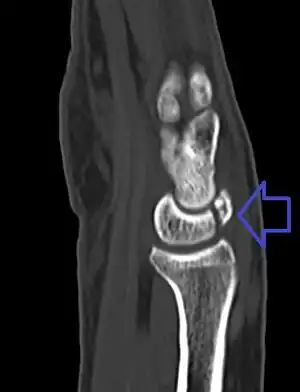

| A lunate fracture as seen on CT scan of the wrist | |